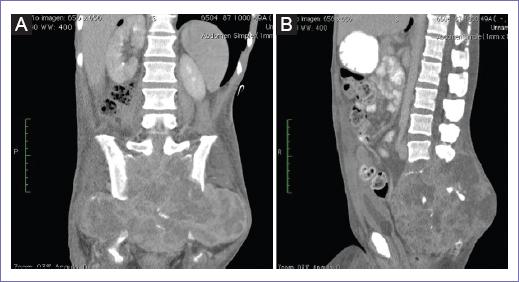

Hombre de 50 años de edad, con historia de 11 meses de evolución, caracterizada por dolor lumbar, parestesias en miembros pélvicos y pérdida progresiva de la fuerza muscular. En los últimos seis meses, exacerbación del cuadro. Inicialmente fue valorado fuera de la institución, documentándose tumor de sacro por tomografía. Se tomó biopsia, que reveló un TCG, se consideró no candidato a tratamiento quirúrgico y se le suministraron dos ciclos de quimioterapia con doxorubicina y dacarbazina, con nula respuesta y morbilidad hematológica, aunándose dolor pélvico de difícil control. Dos meses antes de la valoración en nuestra unidad presentó paraparesia y pérdida de control de esfínteres, incremento del dolor y escaras por decúbito prolongado. Ingresa a la unidad en malas condiciones generales, desnutrición y dolor refractario al manejo con múltiples esquemas analgésicos, por clínica y tomografía franca progresión del tumor con infiltración a tejidos blandos de la pelvis, exteriorización del tumor en diversos sitios de la pelvis; por tomografía, tumor central con evidente destrucción del sacro, infiltración a recto, vejiga y afectación de ambas articulaciones sacroiliacas, extensión hasta L2 (Fig. 1 A y B). Se realiza resonancia magnética, que corrobora los mismos hallazgos.

Figura 1 A: tomografía, tumor central con evidente destrucción del sacro, infiltración a recto, vejiga y afectación de ambas articulaciones sacroiliacas, extensión hasta L2. Corte coronal. B: tomografía, tumor central con evidente destrucción del sacro, infiltración a recto, vejiga y afectación de ambas articulaciones sacroiliacas, extensión hasta L2. Corte sagital.